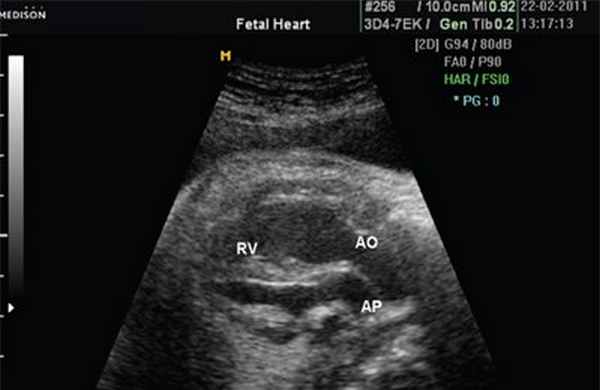

Рис. 7. Транспозиция магистральных сосудов.

Рис. 8. Транспозиция магистральных сосудов, стрелками показаны ветви легочной артерии.